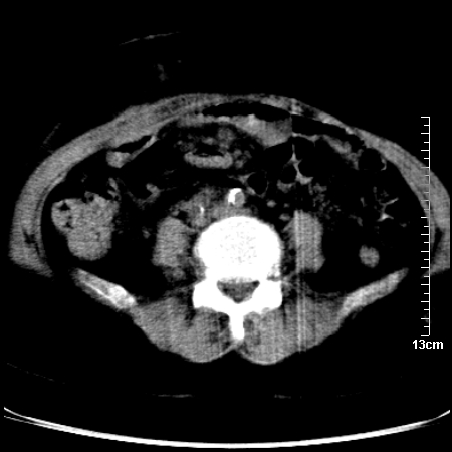

术前的疏忽,手术前诊断阑尾炎,但是没有常规做b超,导致术后1周检查发现 1。实性包块?2。腹腔术后脓肿?

病史:病人一周前诊断阑尾炎,未做b超,手术发现阑尾化脓,(没有留意有无包块),术后1周病人发热,血象:1.6万,做b超发现,随ct检查,上传图片

巨大囊实性包块,边界大部尚清楚,不太像脓肿的表现。应该做个增强检查除外盆腔肿瘤。

脓肿可能性大. 因回盲部区域化脓性兰尾切除残端感染改变征像与实性肿块关系密切.肿块上界至右下腹,下界至盆腔膀胱上缘, 如果是实性肿块在兰尾术中可能就会发现. 所以术后一周病人高烧, 白细胞增高,临床表现支持脓肿.

盆腔一边界大部份清晰囊实性肿块,其周腹脂未见确切异常,其一端与右侧附件相连。考虑右侧附件肿瘤。

如果能进行肠道准备就好了!盆腔内巨大囊实性包块,右前缘与周围肠管分界不清,病灶内前部的气体是否为肠管内气体形成的假象不能确定。

这么大一包快手术当中没有发现?值得怀疑!结合化脓性阑尾炎病史,首先考虑脓肿!不排外附件来源的肿瘤,建议增强扫描!!